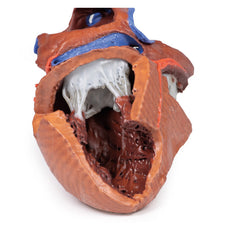

In the middle

mediastinum the

heart, within the pericardium, is transacted to reveal the left atrium posteriorly, then moving clockwise, the

aortic valve, right ventricle and the right atrium.